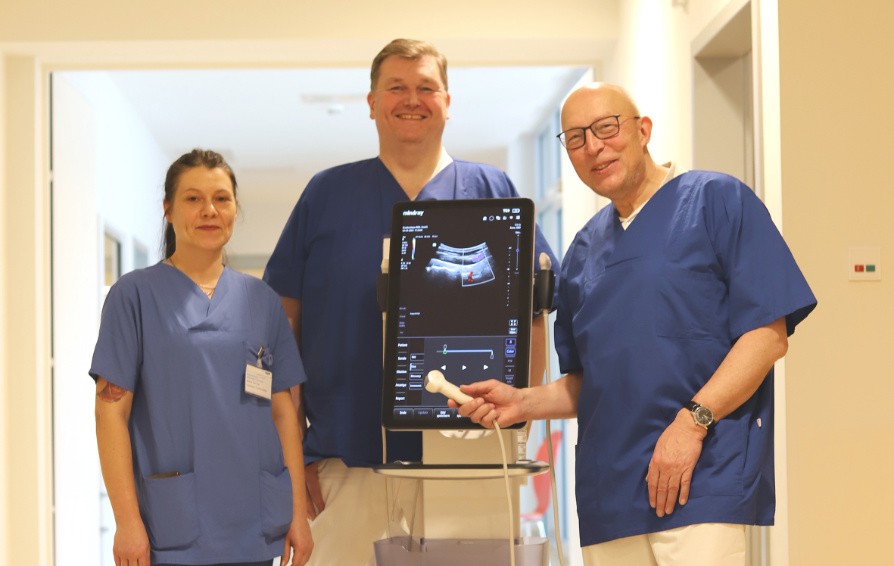

![switch-off-pain-ultrasound-controlled-trunk-blocks.thumb.1280.1280 Schmerz abschalten mit ultraschallgesteuerten Rumpfblockaden]() Ultraschall | An?sthesieSchmerz abschalten mit ultraschallgesteuerten Rumpfblockaden

Ultraschall | An?sthesieSchmerz abschalten mit ultraschallgesteuerten Rumpfblockaden -